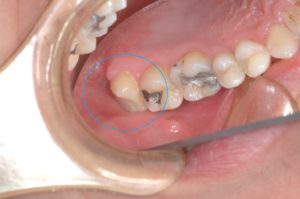

下写真の歯(オレンジ〇)は歯根破折しており抜歯になります。その代わりに親知らず(青〇)を移植する計画としました。

上顎の親知らず(青〇)を抜歯しました。